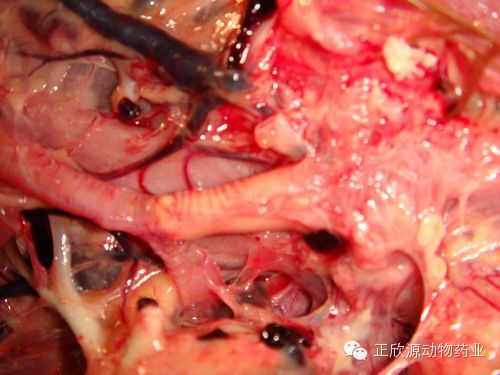

蛋鸡传染性支气管炎感染通常可见卵泡系带松弛,卵泡呈扁圆或椭圆形,输卵管子宫部粘膜水肿。雏鸡阶段感染传染性支气管炎的假母鸡剖检可见卵巢发育正常,腹腔常可见排出的卵泡和破裂于腹腔的卵黄;输卵管发育不良或者输卵管伞到狭部之间没有发育,仅保留子宫部和阴道部,输卵管内积水。

“假母鸡”剖检后卵巢发育良好,但输卵管伞部、膨大部缺失,峡部、子宫部发育不良(武现军摄)

发育不良的输卵管峡部以上部分闭锁,输卵管内积水(武现军摄)

输卵管峡部以上闭锁,并形成水泡。水量多者可达500毫升以上(武现军摄)